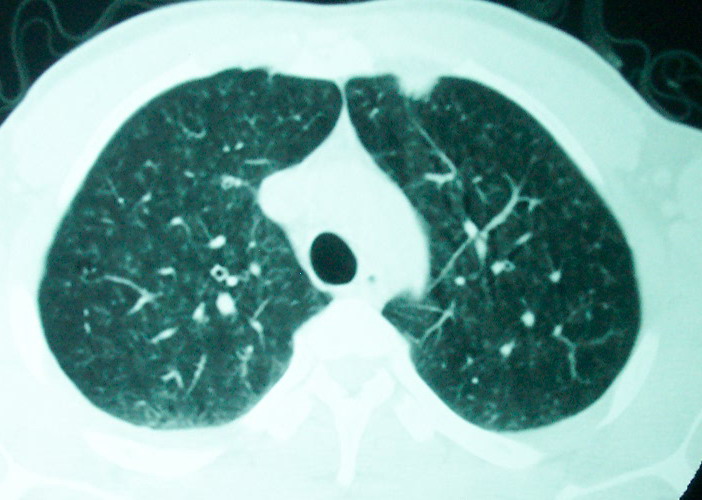

m      37y      发热   咳脓痰月余      ct肺脓肿但住院抗炎治疗后双肺内结节不知该如何解释

治疗后见左肺下野病灶较前缩小但双肺内结节影似无变化请较各位老师该如何下结论    治疗前wbc14.5 治疗后wbc 11.0

血源性肺脓肿,一般由原发感染灶引起脓毒败血症,在肺部形成小脓肿,病变变化快,容易形成肺气囊,脓气胸,主要与转移瘤鉴别,通过临床病史可分

结合临床发热,咳痰考虑为血源性肺脓肿,不过双肺结节又在肺的边缘,还是小心一点,抗炎后复查吧

除了肺内多发结节和左肺下叶的浓疡病灶,还应注意满肺散在的小结节影,还有右上肺前段支气管内膜不光整这些细节,结合病史,肺内多发结节应考虑结核性肉芽!